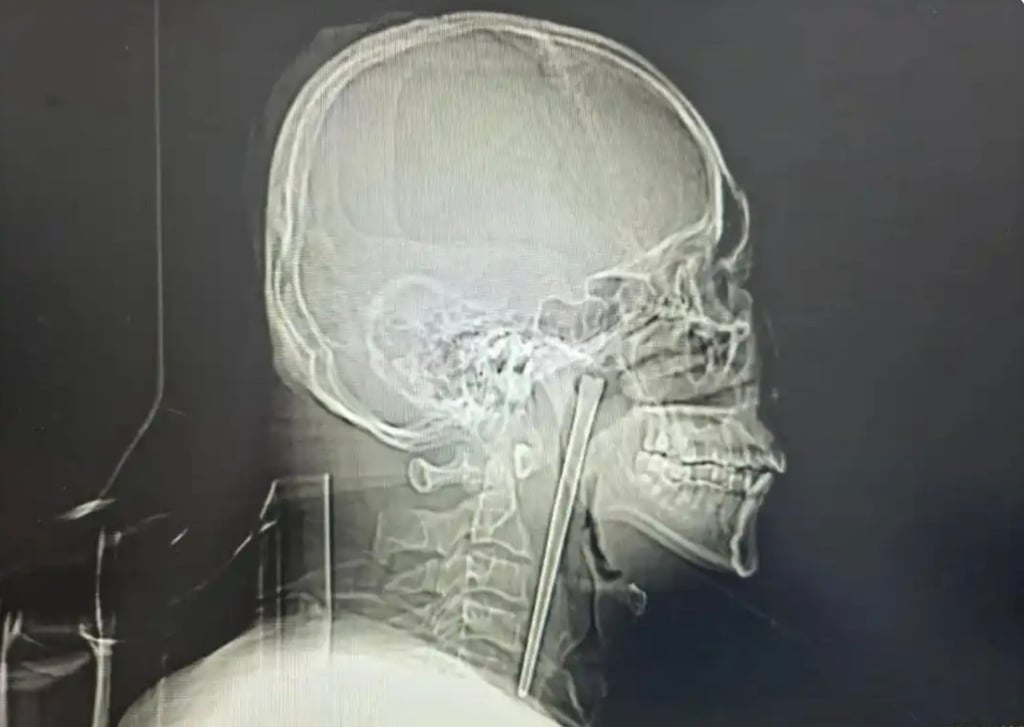

Một người đàn ông họ Vương tại Trung Quốc vừa trở thành tâm điểm chú ý trên mạng xã hội sau khi các bác sĩ phát hiện và lấy ra một chiếc đũa kim loại dài 12 cm đã nằm trong cổ họng ông suốt 8 năm. Câu chuyện không chỉ khiến nhiều người kinh ngạc mà còn đặt ra những câu hỏi về nhận thức sức khỏe và tâm lý sợ hãi phẫu thuật của bệnh nhân.

Trước việc bệnh nhân tiếp tục từ chối phương án rạch cổ, các bác sĩ đã lựa chọn một giải pháp khác ít xâm lấn hơn, đó là tiến hành phẫu thuật qua đường miệng. Ca mổ được thực hiện cẩn thận và thành công khi chiếc đũa kim loại dài 12 cm được lấy ra mà chỉ gây chảy máu ở mức tối thiểu.

Các bác sĩ tại đây ban đầu không khỏi bất ngờ khi nghe bệnh nhân nói rằng chiếc đũa đã nằm trong cổ họng suốt 8 năm. Kết quả kiểm tra cho thấy dị vật nằm ở vùng vòm miệng mềm, một vị trí nhạy cảm nhưng may mắn là chưa gây tổn thương nghiêm trọng.

Theo đánh giá của đội ngũ y tế, niêm mạc xung quanh vẫn còn nguyên vẹn, các cơ quan liên quan không bị dịch chuyển và dây thanh âm vẫn hoạt động bình thường. Đây được xem là điều hiếm gặp, bởi một dị vật có kích thước lớn như vậy thường dễ gây ra biến chứng nguy hiểm nếu tồn tại lâu trong cơ thể.